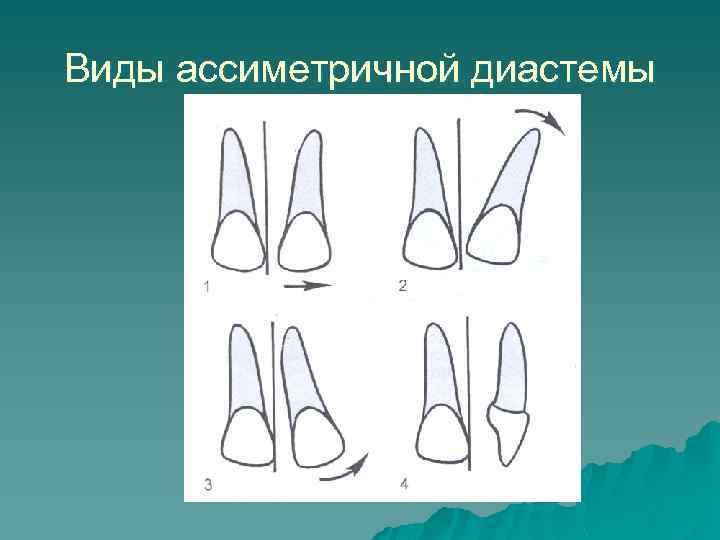

Виды ассиметричной диастемы u Параллельное отклонение коронки и корня резца от средней линии u Более значительное перемещение корня резца, чем коронки u Более значительное латеральное перемещение коронки зуба, чем корня u Смещение резца латерально и его тортоаномалия

Виды ассиметричной диастемы